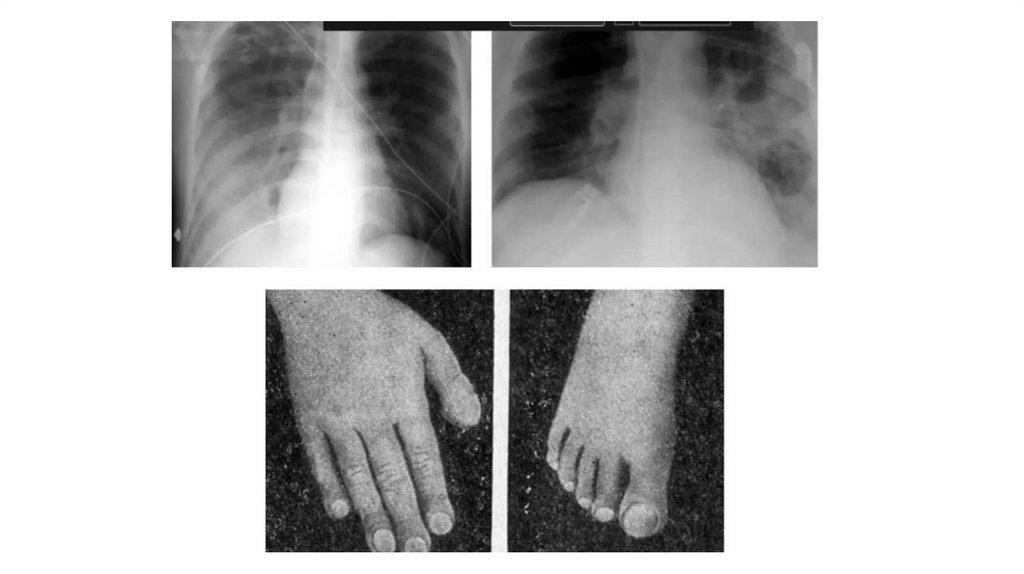

Врожденные и наследственные заболевания легких у детей